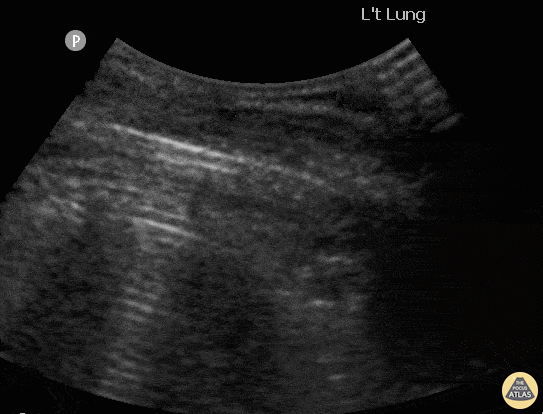

Pulmonary - Pneumothorax with Lung Point

A patient presented with spontaneous pneumothorax; lung point identified on POCUS. ChunYi Tsai, @jerry1231213